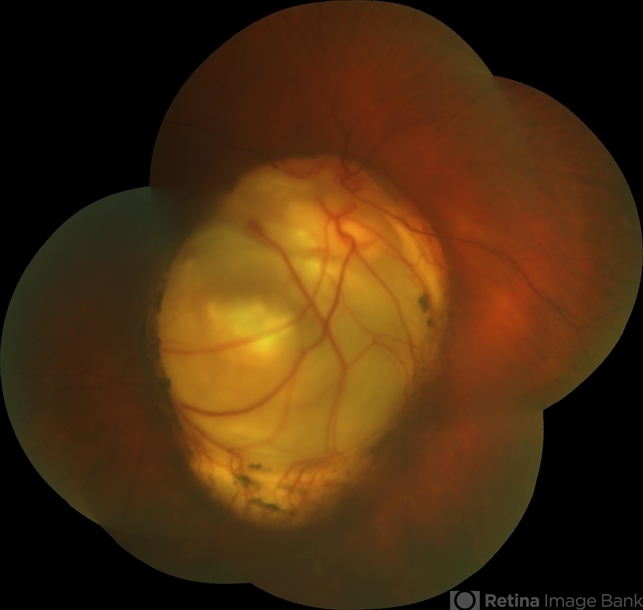

- coloboma of the optic nerve

- Alexandr Stepanov MD, PhD, FEBO, Faculty Hospital Hradec Kralove, Czech Republic

- Coloboma of optic nerve,